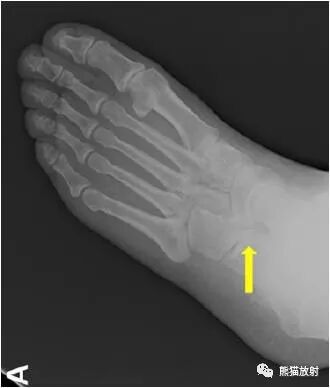

足正侧位平片

拍摄足负重正侧位,45°内斜位,跟骨轴位X线片。

跟舟联合在侧位X线片上呈现食蚁兽鼻征,拍摄45°内斜位X片观察跟舟联合